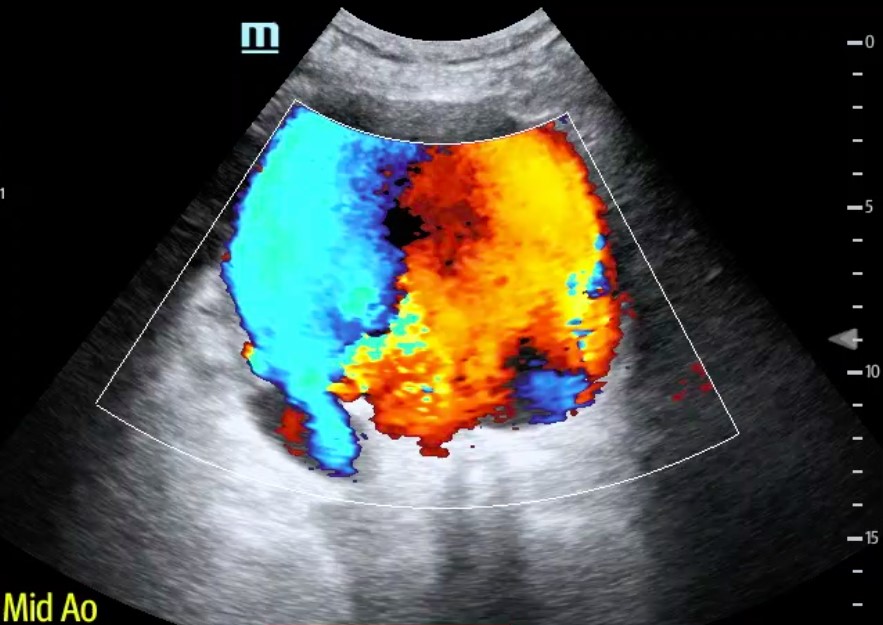

Point-of-care ultrasound (POCUS) performed at the patient’s bedside demonstrated a large, 11 cm, abdominal aortic aneurysm (AAA) with visible echogenic turbulent blood flow (Figure 1, Video 1). With the assistance of Color Doppler, we were able to confirm that the AAA had ruptured with active hemorrhage (Figure 2, Video 2). Volume resuscitation with IV fluids and blood products was initiated, while Vascular Surgery consult was called and arrived at the bedside within 15 minutes. The patient was taken emergently to the OR for successful endovascular aortic repair.

Figure 2. AAA Color Doppler.